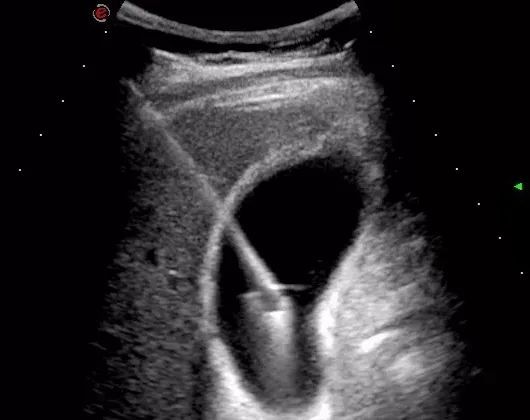

肝胆外科中心王华副主任医师收到会诊需求后,发现患者有腹膜炎刺激征、寒战高热,白细胞明显升高,胆囊肿大张力高、濒临坏疽穿孔。对于急性重症脑梗患者,一旦胆囊穿孔会危及生命。考虑患者重症胆囊炎,存在急性脑梗、全身情况差,无法耐受手术治疗,王华医师当即决定予以行经皮经肝胆囊穿刺引流术。穿刺时发现胆汁呈黑色,喷射状泄出,可见胆囊压力极高,如不穿刺,随时有穿孔的风险。穿刺后第二天患者体温恢复正常,腹部平坦柔软,白细胞也明显下降。

经皮经肝胆囊穿刺引流术是一种微创治疗手段,能够迅速达到胆囊减压的作用,主要用于治疗急性化脓性胆囊炎、急性重症胆囊炎以及胆总管梗阻合并胆囊肿大者,尤其适用年老体弱患者,或合并严重疾病不能耐受手术的患者。